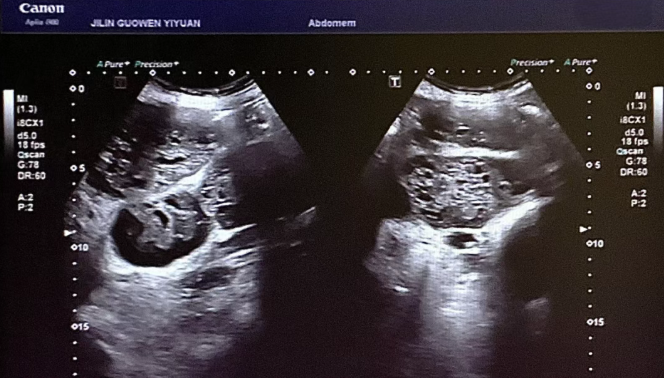

患者錢女士(化名),65 歲,因有高血壓病史而定期進(jìn)行體檢。在超聲檢查時(shí),醫(yī)生發(fā)現(xiàn)其腎臟存在占位性病變。超聲科團(tuán)隊(duì)借助高分辨率超聲成像技術(shù),清晰地觀察到腎臟內(nèi)的異?;芈晠^(qū),再結(jié)合血流信號(hào)分析,高度懷疑該病變可能為惡性腫瘤。為進(jìn)一步明確診斷,團(tuán)隊(duì)在超聲引導(dǎo)下進(jìn)行精準(zhǔn)穿刺,獲取病理組織。最終,病理報(bào)告確診該病變?yōu)?“小圓細(xì)胞惡性腫瘤”。

小圓細(xì)胞惡性腫瘤是一類較為少見的惡性疾病,常見于兒童及青少年,而發(fā)生在老年患者腎臟的情況則更為罕見。此類腫瘤具有很強(qiáng)的侵襲性,早期診斷對于治療方案的制定以及患者的預(yù)后都至關(guān)重要。錢女士雖然沒有出現(xiàn)典型癥狀,腹部查體也未觸及包塊,但得益于超聲科的細(xì)致檢查,病灶被及時(shí)發(fā)現(xiàn),這為后續(xù)的治療贏得了寶貴時(shí)間。